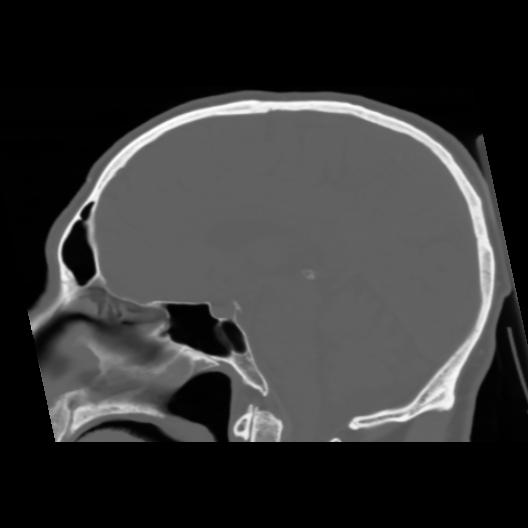

6 CEREBRO,,Sagittal,3.000,CEREBRO,Sagittal,